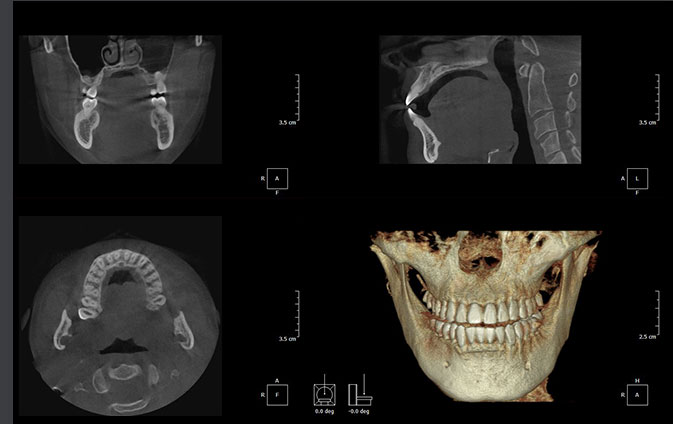

歯科用CTを用いた正確な診断

歯科用CTは、顎の骨の状態を3D画像で詳細に把握できる先進的な機器です。これにより、骨の厚さや密度を正確に確認でき、インプラント治療の計画をより精密に立てることができるため、治療の成功率を大幅に向上させます。

複雑な歯の根の状態も精密に診断できるため安全なインプラント治療に必須です。

シミュレーションソフトで事前確認

取得したCT画像をもとにシミュレーションソフトで治療計画を作成し、インプラントの埋入位置や角度を事前に確認します。このシミュレーションにより、手術の正確性が増し、歯茎を切開する範囲を最小限に抑えることが可能です。その結果、術後の治りが早まり、身体への負担も軽減されます。